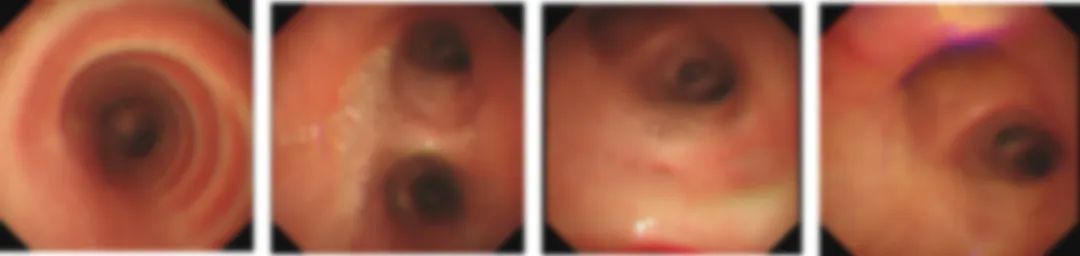

气管镜检查提示,主气管粘膜溃疡和气道多个丘状突起,形似一个个“小蘑菇”;经过肺泡灌洗液培养,提示烟曲霉,病理符合真菌感染改变;

△治疗前(气管镜):双肺支气管粘膜散在分布的黄白色结节状突起,就像沿路长了一个个小蘑菇!

△治疗后(气管镜):主气管粘膜的溃疡病变、隆突的疣状突起及气道内的大部分黄白色结节状突起都明显好转。